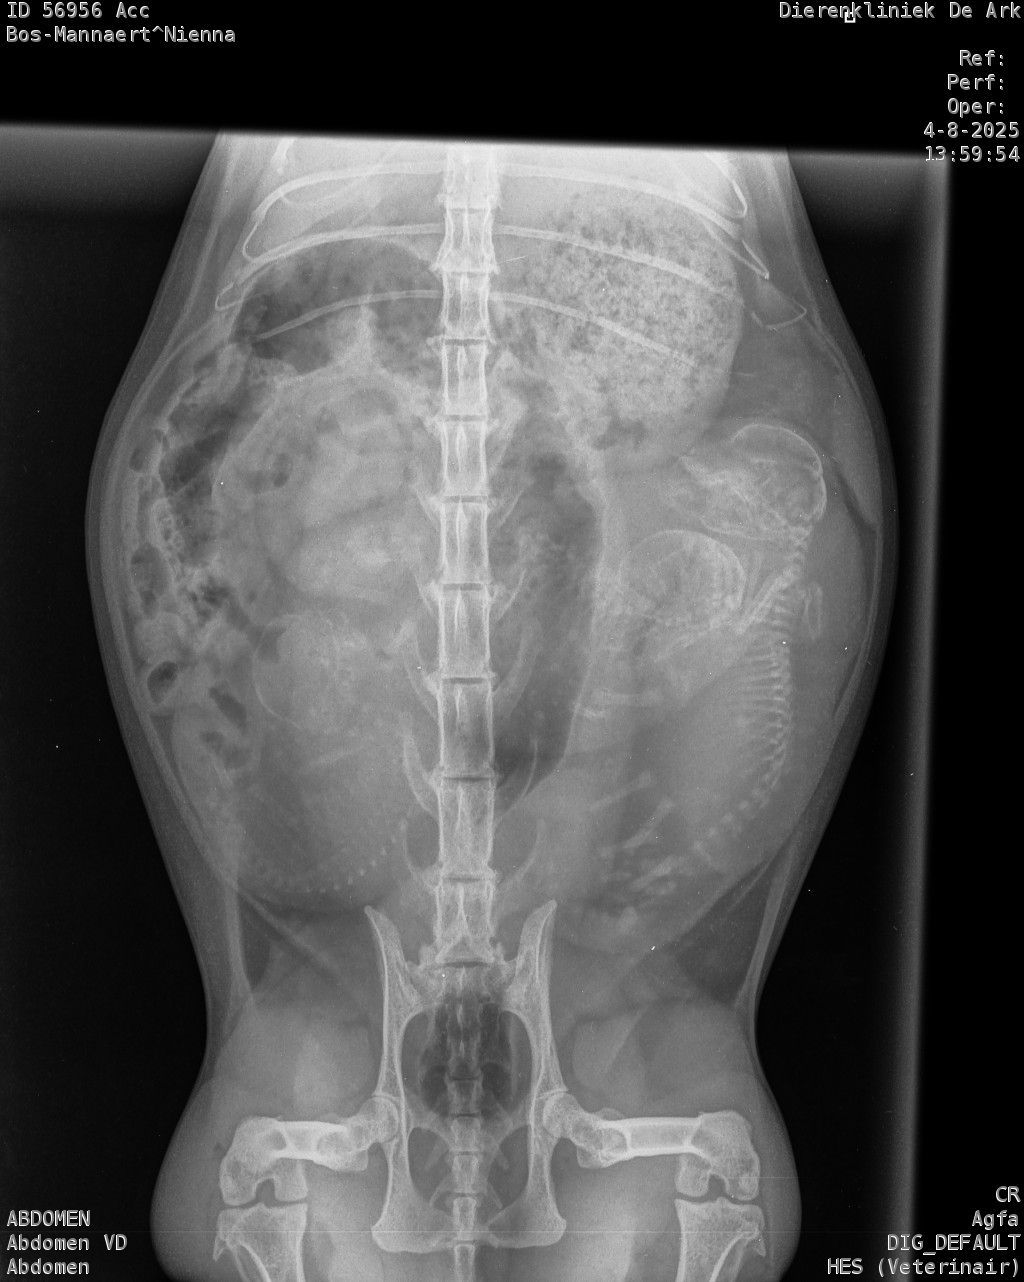

Zondag zag het er naar uit dat Nienna haar melkproductie een beetje op gang kwam. Maandag hebben we dan ook gelijk een checkup gepland en is er een foto gemaakt.

Er waren duidelijk 3 kittens zichtbaar. Dus kreeg ze gelijk een rustig plekje in de woonkamer. Maandag avond was het al aan het rommelen, uiteindelijk zette de bevalling pas goed door in de nacht van dinsdag op woensdag 6 augustus.

Op de foto was te zien dat de 3 kittens waarschijnlijk allemaal in de stuit lagen. Gezien ik niet wist hoe ver ze al was in de dracht en of de kittens groot zouden zijn konden we niet meer dan afwachten.